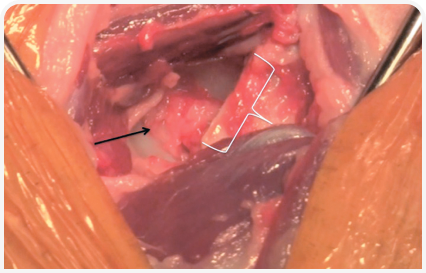

Для достижения отличных результатов ОГБК критически важно правильное проведение хирургической операции. К капсуле тазобедренного сустава осуществляется краниолатеральный доступ. Проводится артротомия путем рассечения суставной капсулы непосредственно над ее входом в шейку бедренной кости. После пересечения круглой связки головка бедренной кости поворачивается кнаружи. Для того чтобы приподнять головку бедренной кости относительно вертлужной впадины и защитить от повреждения седалищный нерв, расположенный каудально и в непосредственной близости от шейки бедренной кости, может использоваться такой инструмент, как крючок для стерилизации.

Для проведения остеотомии может применяться небольшая электропила, пила Джильи или остеотом с молотком; в некоторых случаях кость может оказаться очень мягкой или даже сломанной, и в такой ситуации для удаления оставшейся части головки бедренной кости возможно применение костных кусачек. Для обеспечения правильной антеверсии головки и шейки бедренной кости бедро должно быть адекватно повернуто кнаружи. Этого можно достичь путем фиксации скакательного сустава (пяточной кости — tuber calcis) к латеральной стенке грудной клетки. Остеотомия проводится от основания большого вертела к третьему вертелу бедренной кости (Рис. 3). После резекции головки и шейки бедренной кости участок резекции следует пальпировать для выявления каких-либо острых фрагментов на оставшейся кости, обычно на каудомедиальной стороне остеотомированного участка бедренной кости.